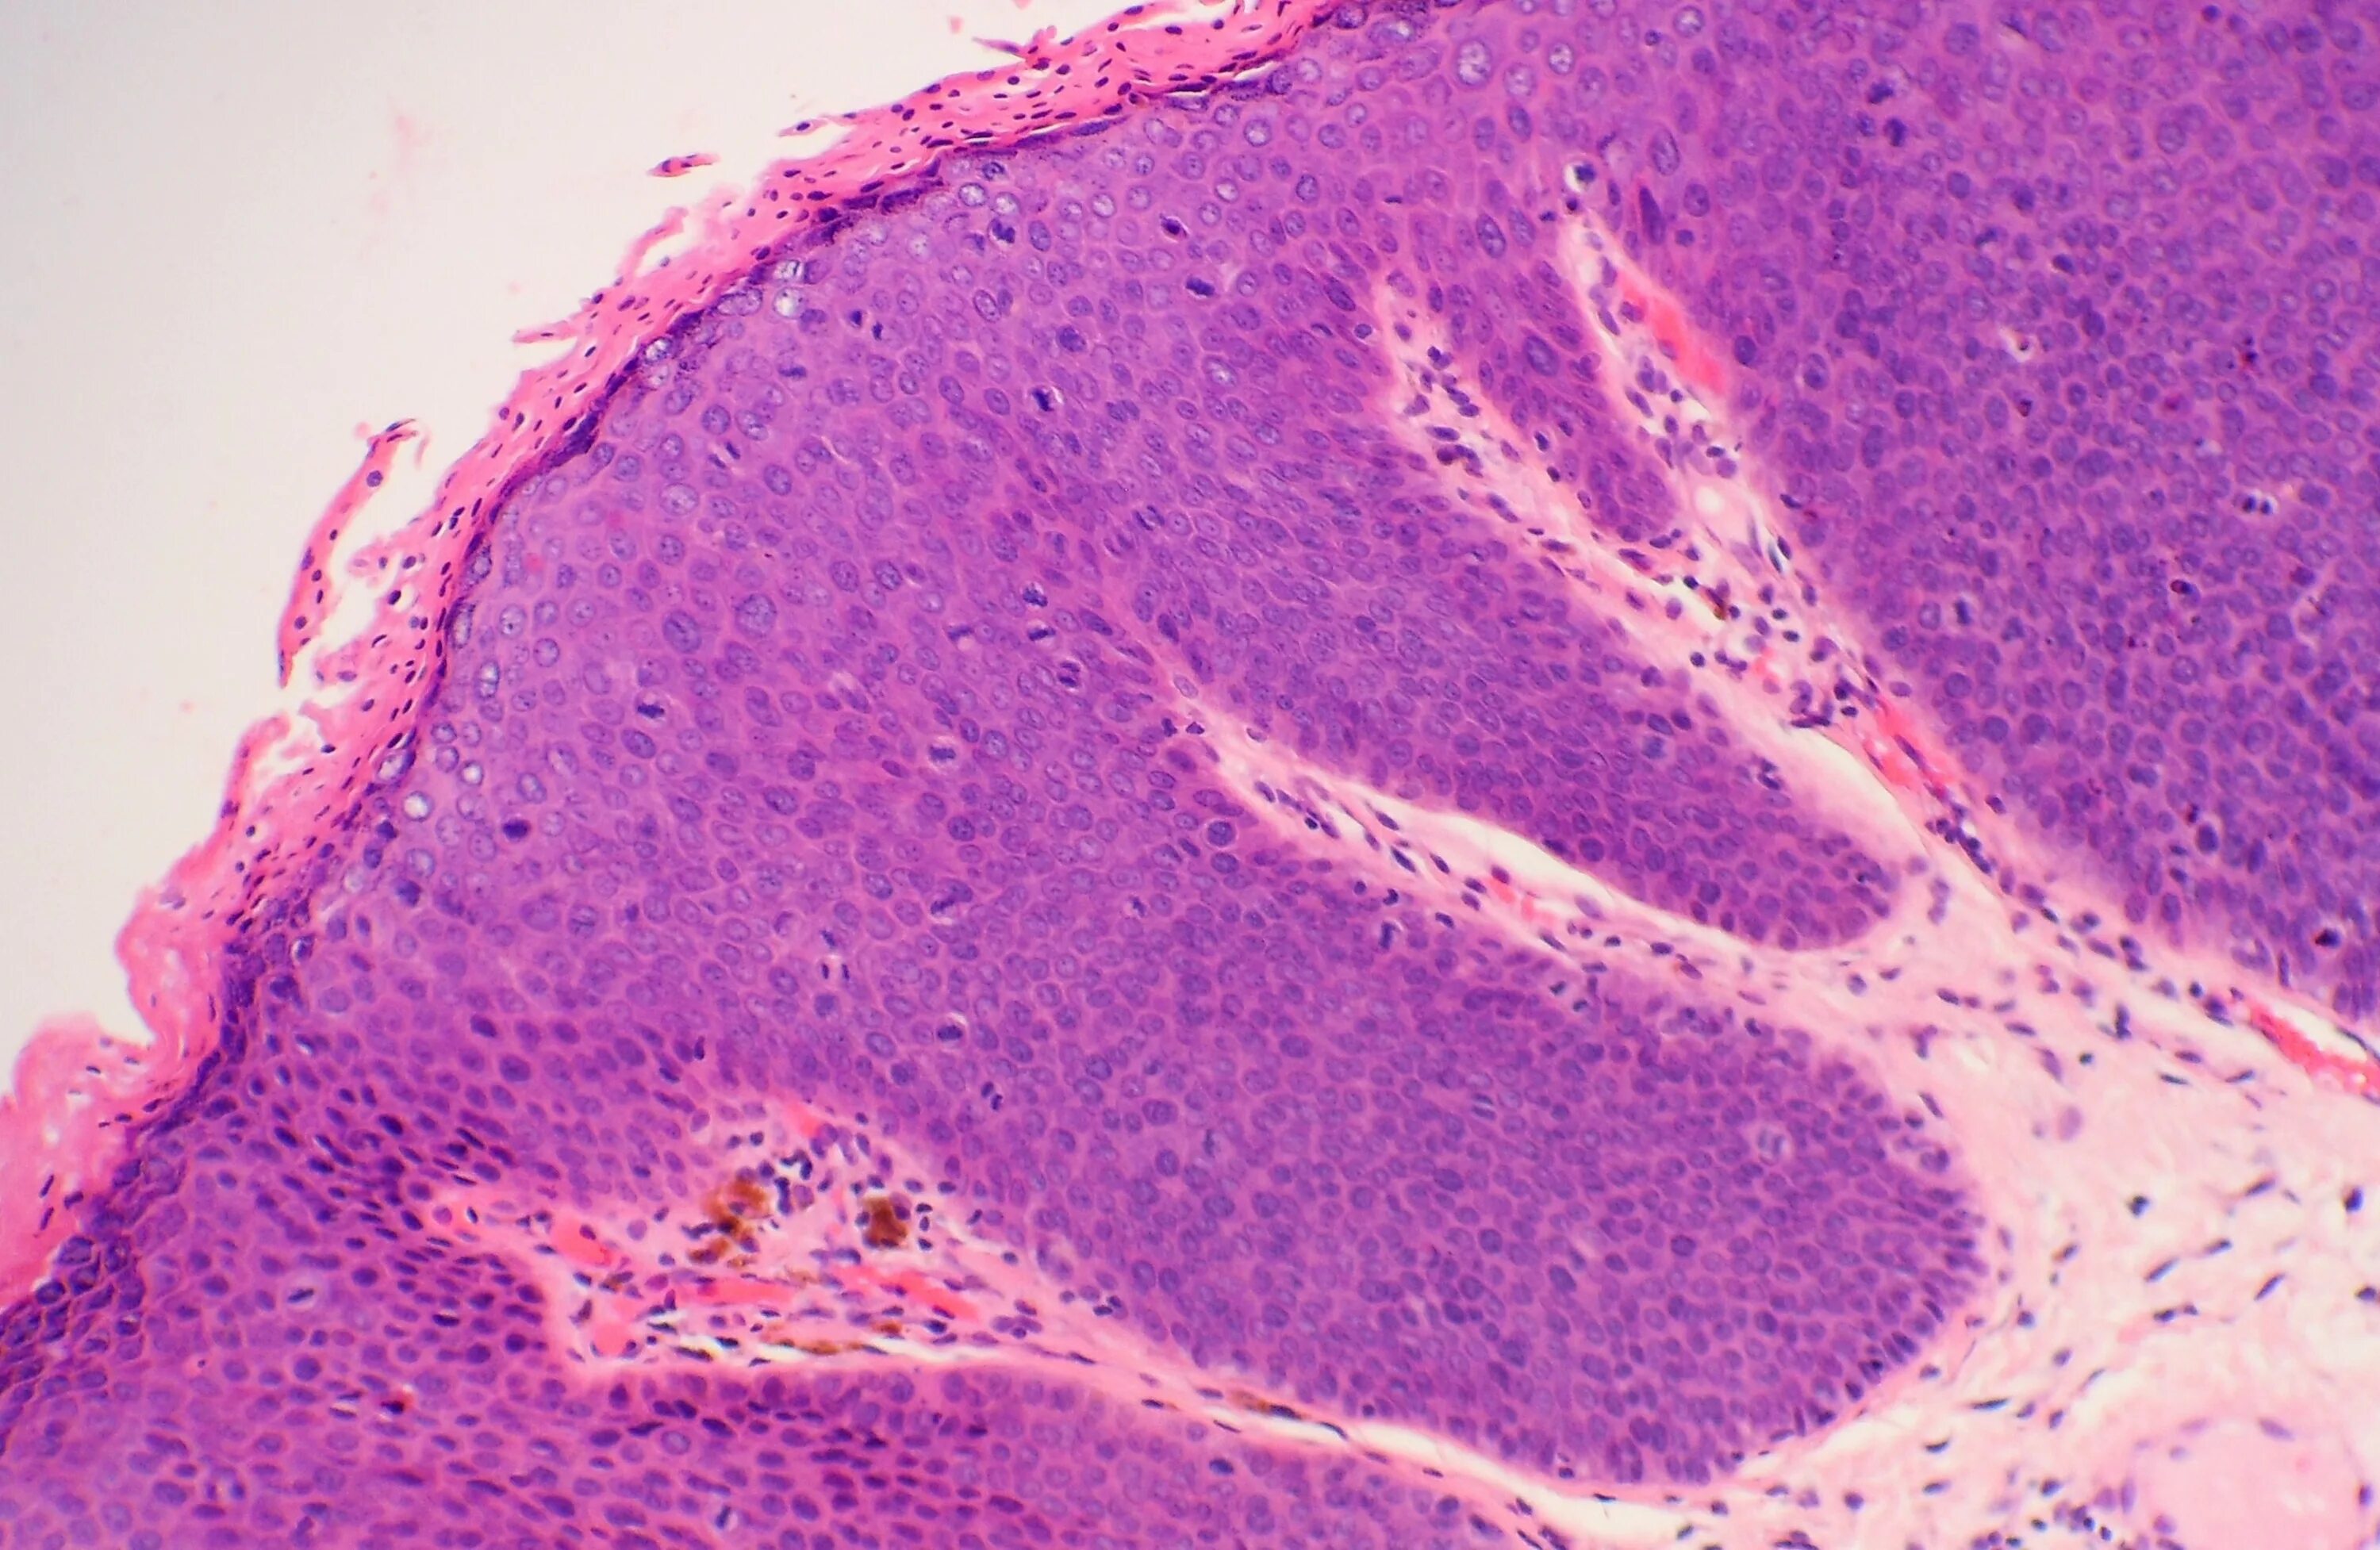

Высокую степень интраэпителиального